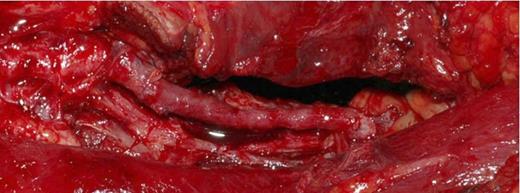

The popliteal artery was explored. (Figure 5) The proximal popliteal artery was found to have a 1cm x 0.5cm wall defect adjacent to the bony exostosis. (Figure 6)The exostosis was excised and the 4cm of diseased artery repaired with end-to-end interpositional long saphenous vein graft. (Figure 7)

Intraoperative Photograph showing the end to end interpositional long saphenous vein graft